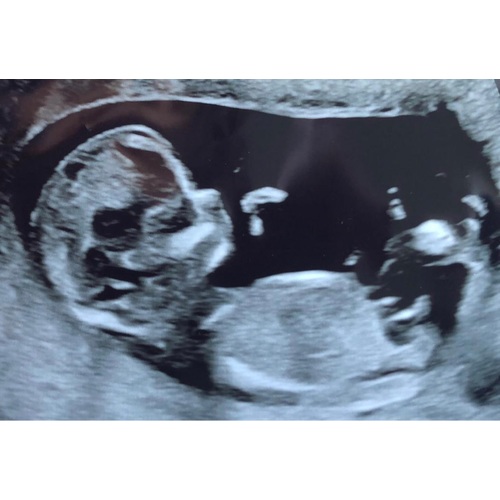

Wat denken jullie meisje of een jongetje.. spannend!

Jongen denk ik, ook de nub馃挋

Wat denk je van mijne ?

Nouja volgens nub test is de kans groot dat jij een meisje krijgt xx